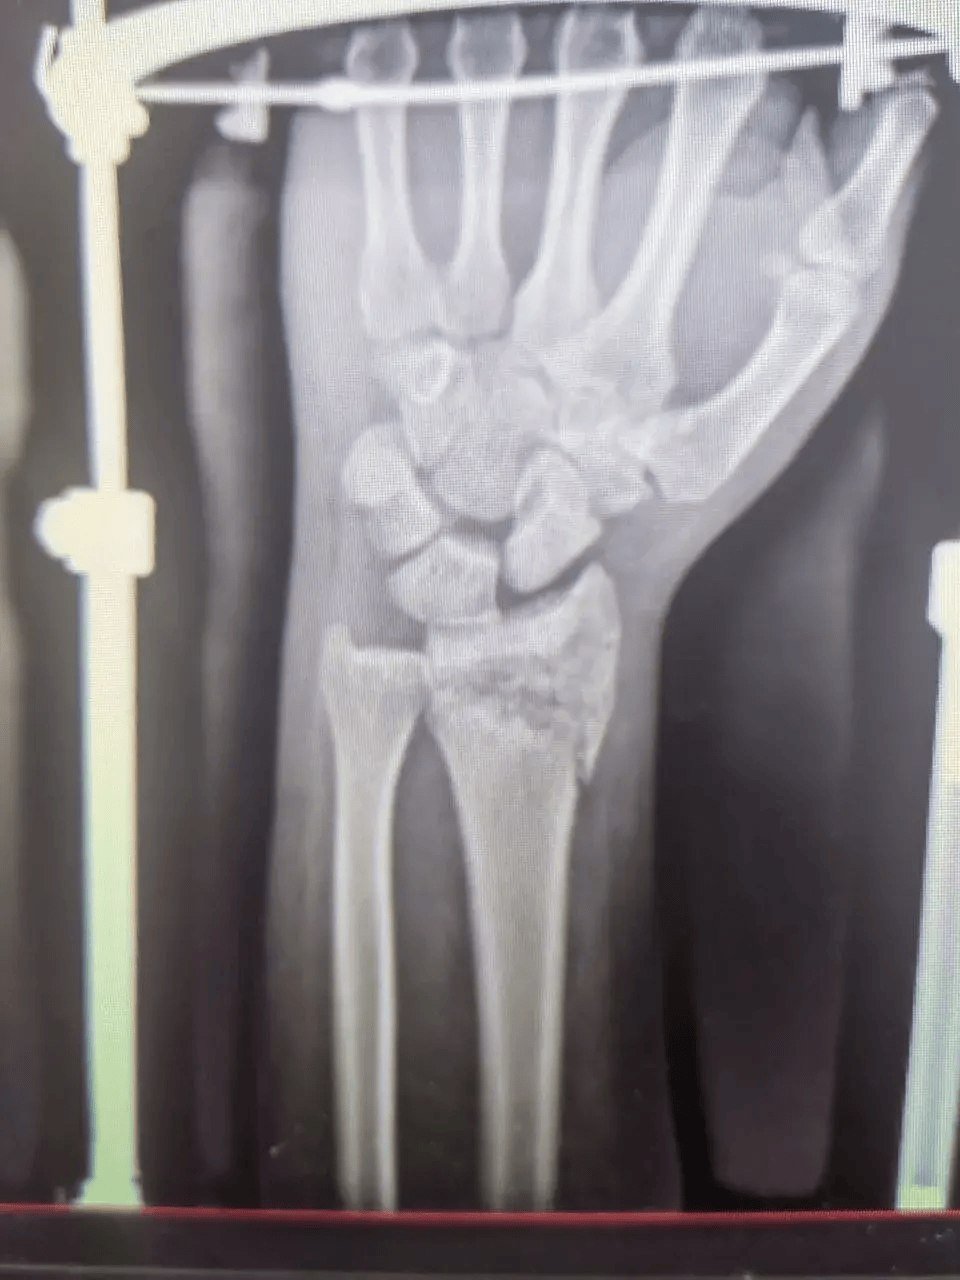

Мужчина 1972 года рождения получил множественные переломы и другие серьёзные травмы. Его лечением занималась команда специалистов разных профилей. Челюстно-лицевые хирурги провели шинирование, травматологи-ортопеды выполнили операцию на правой локтевой кости и восстановили левую лучевую. Также пациент проходил лечение у нейрохирургов и неврологов.